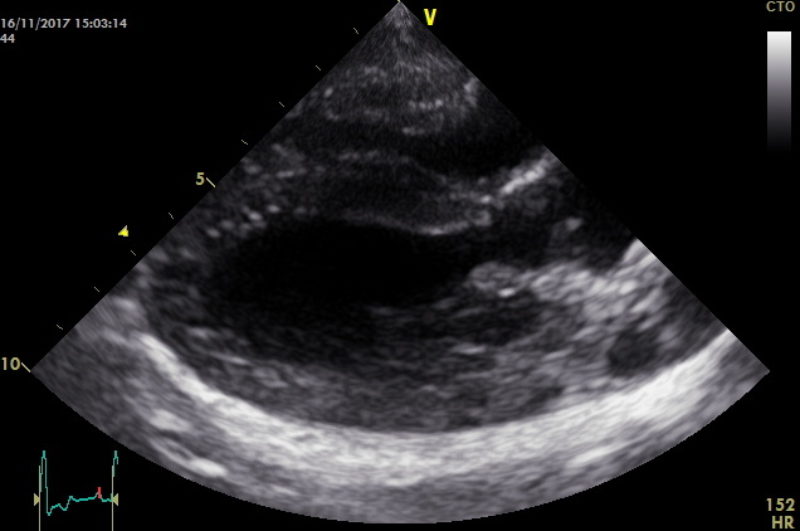

Bei der ersten Herzultraschalluntersuchung war Mailow fünf Monate alt. Dabei wurde im linksventrikulären Ausflusstrakt vor der Aortenklappe eine Einengung festgestellt. Es wurde eine geringgradige Subaortenstenose (SAS) diagnostiziert. Aortenstenosen verschlimmern sich häufig im Laufe des Wachstums, daher sollten auf jeden Fall auch bei anfänglich geringgradigen Befunden Folgekontrollen durchgeführt werden. Mailows Befund blieb relativ stabil. Bei seiner letzten Untersuchung war Mailow fast drei Jahre alt.  Man maß in der Aorta eine maximale Blutflussgeschwindigkeit von 3 m/s (dies entspricht einem Druckgradienten von 36 mmHg). Bei gesunden Hunden ist die Blutflussgeschwindigkeit in der Aorta in der Regel unter 1,8 m/s (entspricht ca. 13 mmHg). Mit Hilfe der Flussgeschwindigkeit beziehungsweise des Druckgradienten kann man den Schweregrad der Aortenstenose einteilen.

Durch die Einengung des Ausflusstraktes der linken Hauptkammer kommt es zur Hypertrophie (Verdickung) des Herzmuskels der linken Kammer. Diese war aufgrund der nur geringgradigen Stenose in Mailows Fall glücklicherweise nur sehr milde.